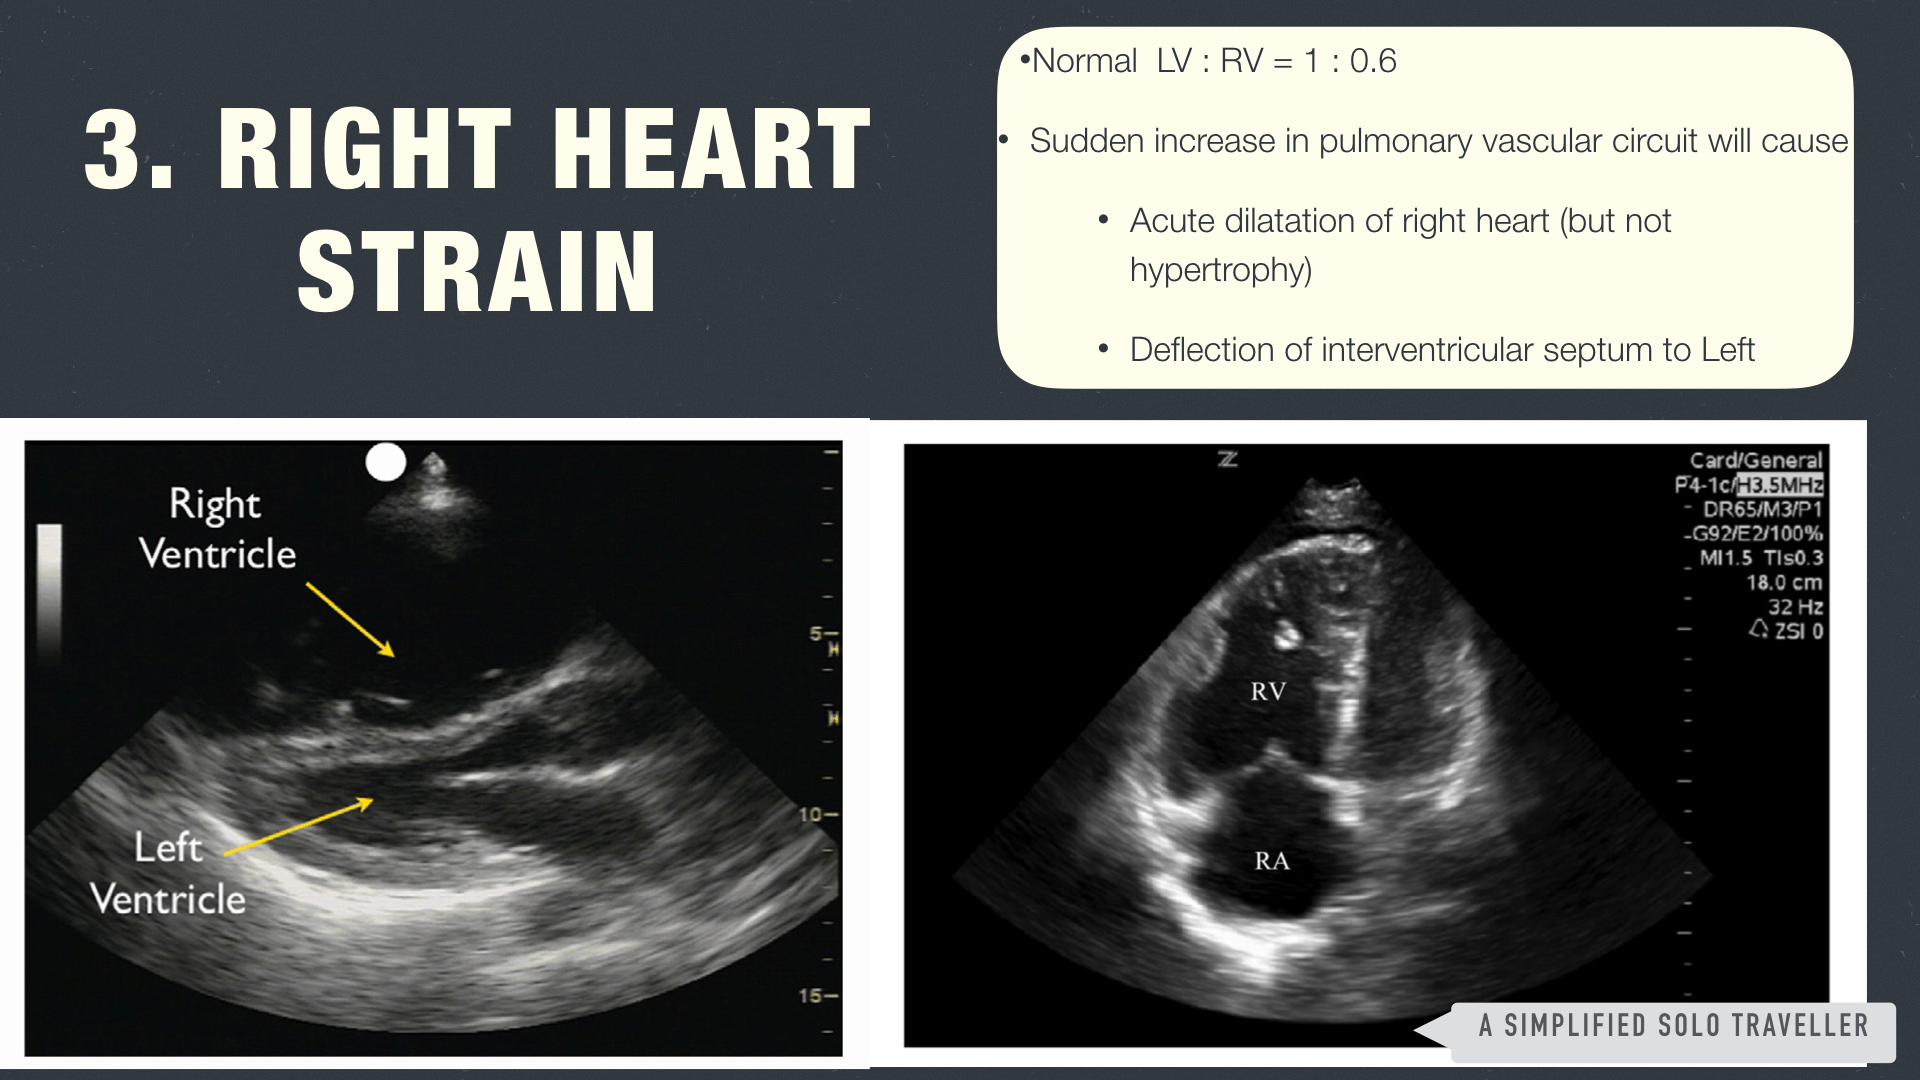

❤️ Strain of pump – right ventricular strain for pulmonary embolism เช่น Right Atrium & Ventricular dilatation (แต่ไม่ใช่ hypertrophy เพราะไม่งั้นอาจเป็น chronic pulmonary hypertension) สัดส่วนปกติของ Left ventricle ต่อ Right ventricle คือ 1 : 0.6 (จำง่ายๆ ว่า LV ต้องใหญ่กว่า RV) มี deflection of interventricular septum to left, Left Ventricular D-Shape หรืออาจพบ intra-cardiac thrombus เป็นต้น